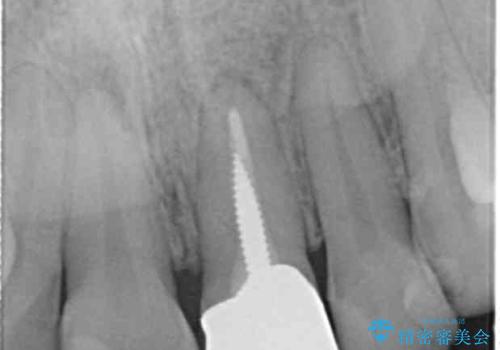

- 長年気になっている前歯の見た目を改善したいと来院されました。

両側の前歯に根尖性歯周炎を認めたため根管治療を行ったのち、ジルコニアクラウンを用いた審美性の改善を計画します。